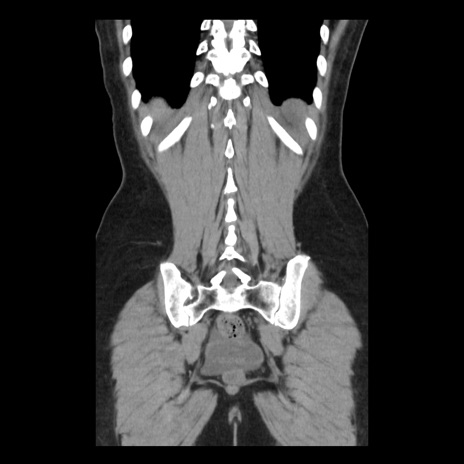

横断像

矢状断像